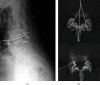

Introduction: Spinal synovial cysts (SSCs) constitute an uncommon degenerative lesion of the spine. They are usually asymptomatic but they may also cause symptoms of variable severity. SSCs are benign growths adjoining the facet joints that may induce low back pain, lumbar radiculopathy, and neurological deficit. There are different treatment options that range from conservative management to interventions like image-guided epidural steroid injection or direct cyst puncture and finally to open or endoscopic spinal canal decompression and spinal bone fusion with/without instrumentation. A discussion of current management options for this unusual disease is presented. Material and Methods. A 52-year-old female patient presented with low back pain and left leg pain. Plain radiography demonstrated instability at the L4-L5 level. Magnetic resonance images (MRIs) revealed a bilateral cystic lesion at the L4-L5 level with associated instability and degenerative disc disease at the level L5-S1. Initially, conservative treatment was performed by aspiration of the left cyst and infiltration with corticosteroids with improvement of the pain for 1 year. After this period, the radicular and the low back pain reoccurred.